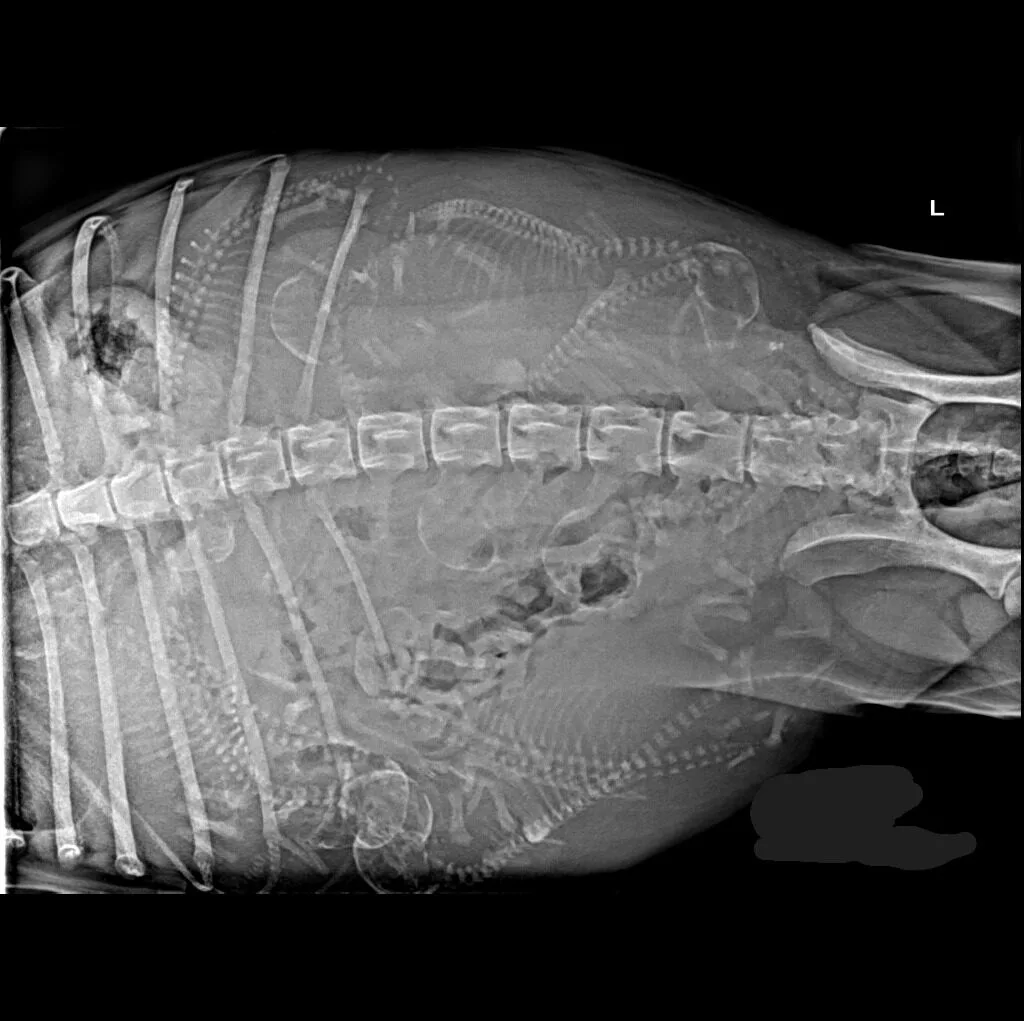

At Grand Ave. Pet Hospital, we utilize digital radiography to diagnose and monitor a wide range of medical conditions in pets. Digital X-rays provide clearer images, faster results, and safer radiation levels, ensuring the best possible care for your furry companion.

Digital radiography offers superior imaging quality and precision compared to traditional X-ray techniques. It allows us to detect hidden health issues early, leading to faster and more effective treatments.

🔹 Abdominal & Gastrointestinal Issues – Detecting obstructions, tumors, or organ abnormalities